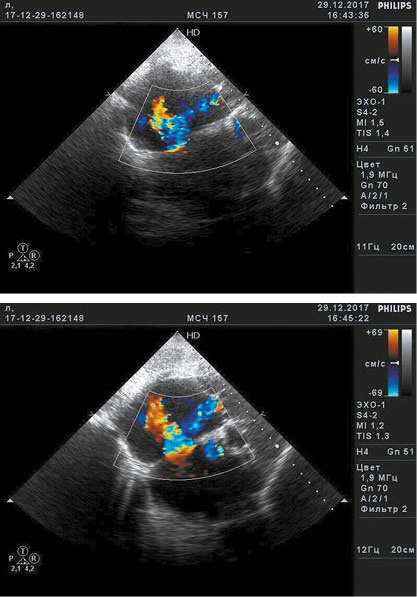

Кроме того, под нашим наблюдением оказался ещё один пациент, которому при скрининговой эхокардиографии был установлен диагноз АЭ. Были обнаружены (рис. 1) удлинение створок ТК, смещение задней и септальной створок к верхушке сердца на 22 мм относительно фиброзного кольца митрального клапана, расширение фиброзного кольца ТК, увеличение объёма правого предсердия (5,29×7,22 см), уменьшение размеров ПЖ, стенки ПЖ утолщены до 4 мм, в верхней трети межжелудочковой перегородки — прерывание эхо-сигнала до 4 мм со сбросом крови слева направо при цветовом допплеровском картировании (рис. 2). Систолическое давление легочной артерии 46 мм рт.ст. Фракция выброса (Симпсон) 36%. Уровень N-концевого пропептида мозгового натрийуретического гормона на момент обращения 650 пг/мл (референсное значение до 150 пг/мл).

Рис. 2. Данные эхокардиографии в режиме цветового допплеровского картирования: сброс крови слева направо